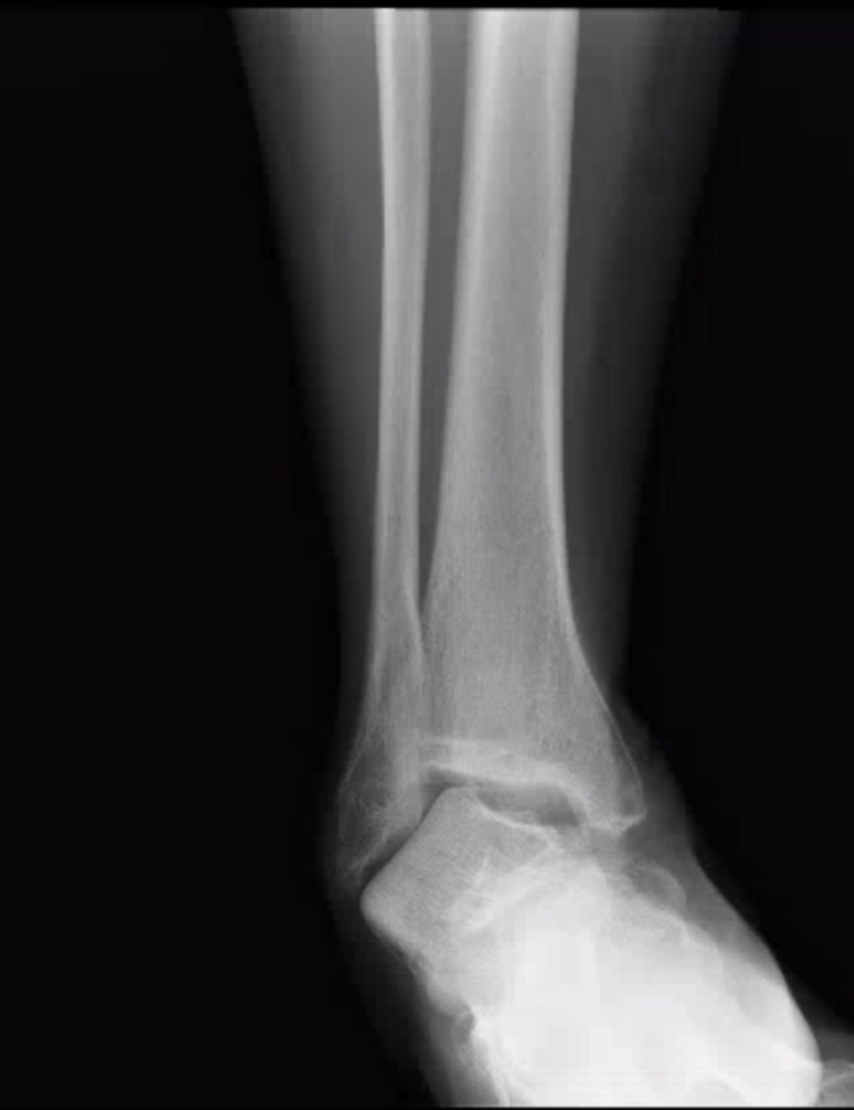

65 yo F presents to the ED with right ankle pain. She reports she twisted her ankle in a pothole. She presents with diffuse pain, swelling and obvious deformity of right ankle. Dorsalis pedis pulse 2+, sensation intact distally.

X-ray is shown. What's the diagnosis? Scroll down for answer.

Answer: Tibiotalar dislocation